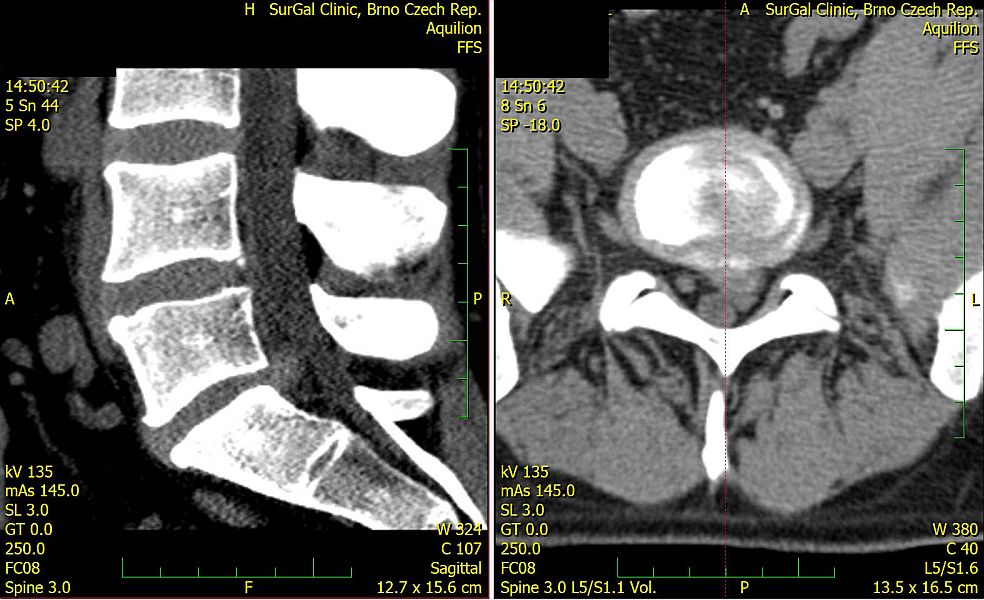

2. Muž, 41 let. Na MR objemná hernie L4/5 velikosti 11mm téměř vyplňující páteřní kanál, útlak nervových kořenů. Opakovaně doporučována operace, kterou pacient odmítl. Jako alternativu zvolil ozonoterapii s aplikací ozonu do disku L4/5 a periradikulárně. Byly aplikovány celkem 3 dávky ozonu. Viz obr.7a

Na kontrolním MR po 6 měsících je patrná výrazná redukce velikosti hernie, vymizely fragmenty, uvolnil se páteřní kanál a do značné míry i nervové kořeny. Subjektivně výrazná úleva téměř k normálu. Viz obr. 7b